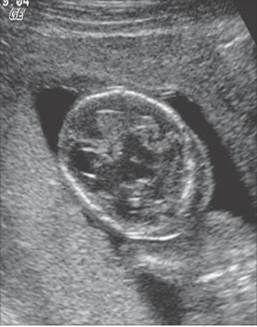

Choroid plexus cysts